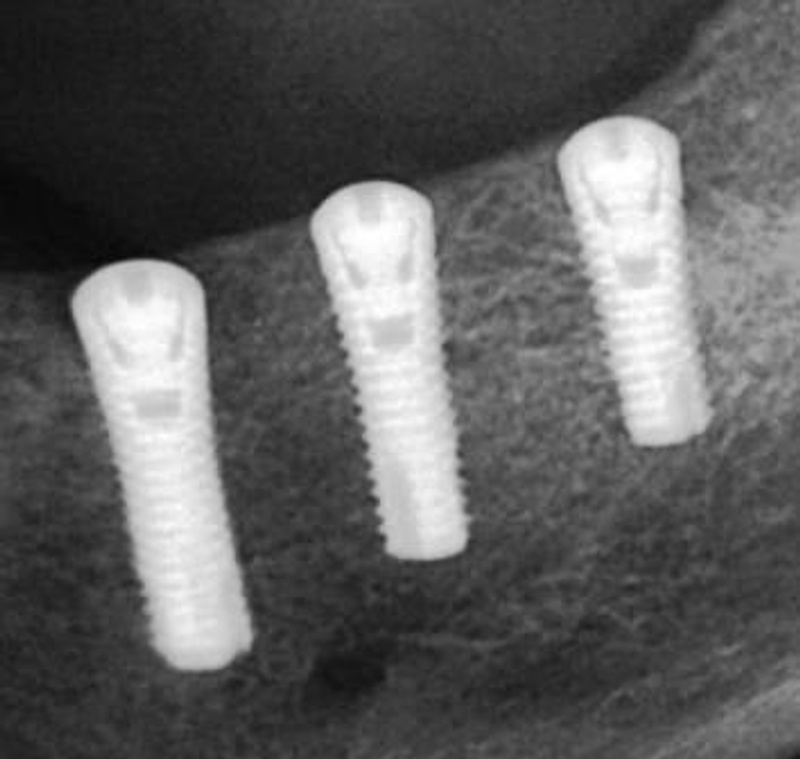

Вообще по идеи лучше всего конечно же ставить импланты ипортные!Ну и какие из этих надежнее или эстетичнее???![]()

Они намного надёжнее и эстетичнеее смотрятся, по сравнению с российскими имплантами!

а рядом зарубежные показаны, вот наподобие что вы картинку мне показали и как выглядят уже готовая работа, поэтому я вот так и написала, эт не правильно???